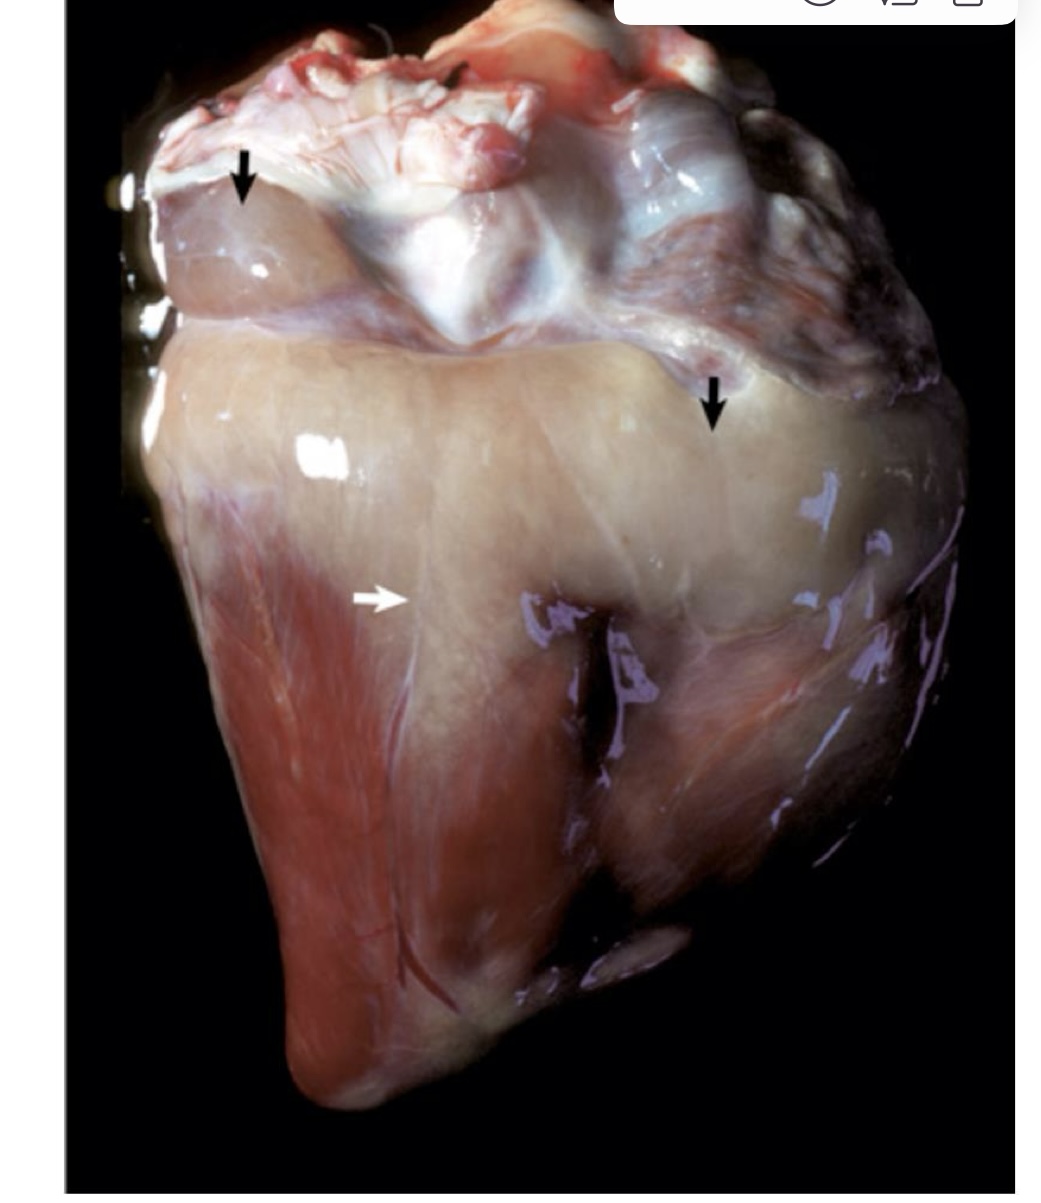

what is this showing?

ulcerative endocarditis → whitish-yellow areas of endocardial mineralization forming plaques that extend to the leaflets

ulcerative endocarditis → white-red, thick, wrinkled area of endocarditis, mineralization, and fibrous tissue caused by uremia